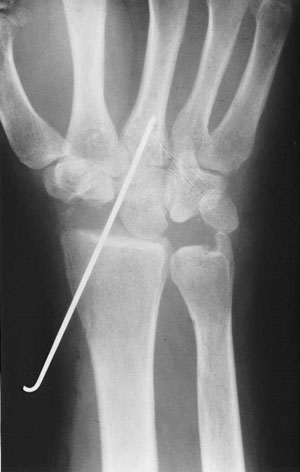

Nosotros realizamos una osteotomía de valguización del radio que consiste en extraer una cuña de base radial y se fija con una placa (figura 9).

Figura 9